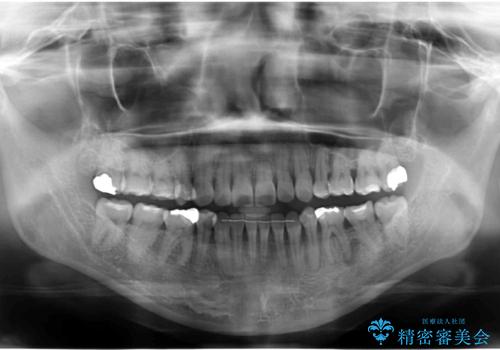

全体的な虫歯治療

- 他院で矯正治療終了後、健診をご希望されました。

神経の治療や詰め物のやり直しなど、全体的な治療を行っています。

左下6番、左上4番は失活していたため、根管治療を行っています。

右上7・左上6:PGAインレー

右上8:PGAクラウン

左上4・左下6・右上56:ジルコニアクラウン

左上7・左下7:emaxインレー

での治療を行っています。

根管治療はDr.大元が行っています。